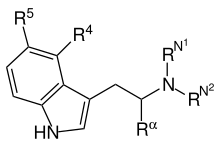

Substituted tryptamines, or serotonin analogues, are organic compounds which may be thought of as being derived from tryptamine itself. The molecular structures of all tryptamines contain an indole ring, joined to an amino (NH2) group via an ethyl (−CH2–CH2−) sidechain. In substituted tryptamines, the indole ring, sidechain, and/or amino group are modified by substituting another group for one of the hydrogen (H) atoms.